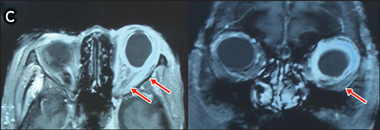

Soon after her second discharge, the patient presented again with persisting and worsening erythema of the left eye, with no associated lid swelling or erythema. A clinical diagnosis of non-necrotising anterior scleritis was made (Figure B), and it was thought that conjunctival lymphoma should be excluded. B-scan ultrasonography revealed fluid in Tenon’s capsule and scleral thickening, consistent with anterior and posterior scleritis (Figure B), and investigations again revealed a raised ESR and CRP level. Screening for tuberculosis (TB) (Mantoux test and chest x-ray), antinuclear antibodies, extractable nuclear antigen antibodies, rheumatoid factor, syphilis, and angiotensin-converting enzyme (an indicator of sarcoidosis) were negative. Screening for Wegener’s granulomatosis with perinuclear antineutrophil cytoplasmic antibodies was positive, but attempted confirmation by screening for antiproteinase 3 antibodies and antimyeloperoxidase antibodies was negative. Magnetic resonance imaging revealed marked high T2 signalling and enhancement of the left sclera, extraocular muscle insertions and distal optic nerve (Figure C). A scleroconjunctival biopsy was performed to exclude conjunctival lymphoma or other uncommon diagnoses, such as tuberculosis and fungal infection. The biopsy revealed a dense inflammatory infiltrate consisting of B and T lymphocytes, plasma cells and occasional neutrophils, with no granulomatous inflammation. Flow cytometry; immunohistochemistry; bacterial, fungal and mycobacterial staining and culture; and TB polymerase chain reaction tests were all negative. Haematological consultation excluded systemic or central nervous system lymphoma.

C: Magnetic resonance images showing high T2 signalling and enhancement of the left sclera, extraocular muscle insertions, and distal optic nerve. |